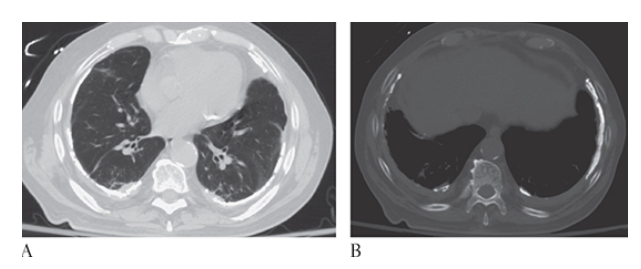

What is A

Coronary Artery Disease. Nonenhanced CT (NECT) shows computer-aided detection and calculation of coronary artery calcification in the right coronary artery left circumflex artery

What is B

Coronary Artery Disease. Nonenhanced CT (NECT) shows computer-aided detection and calculation of coronary artery calcification in the right coronary artery and left anterior descending coronary artery

What is C

Coronary Artery Disease. Nonenhanced CT (NECT) shows computer-aided detection and calculation of coronary artery calcification in the right coronary artery